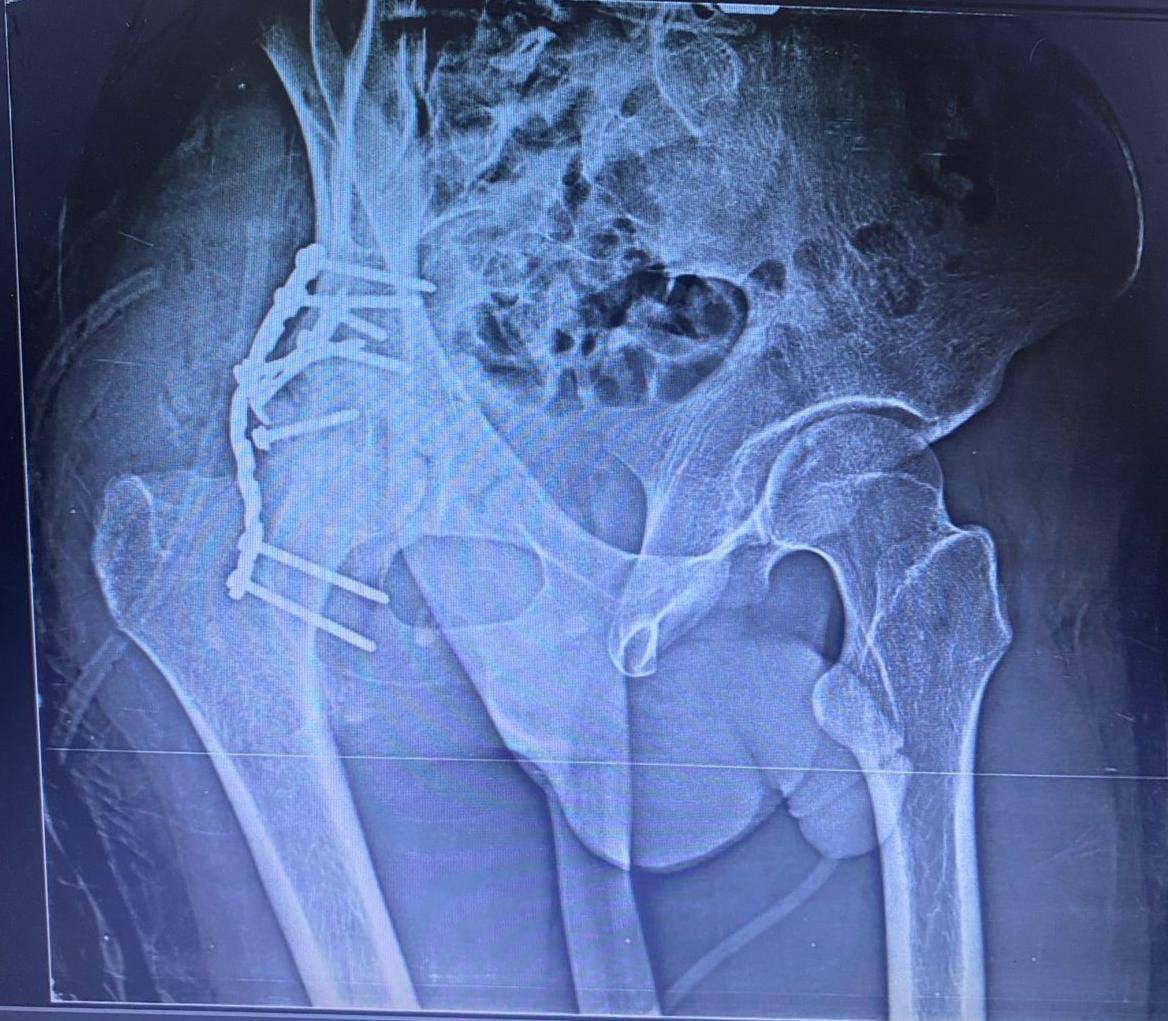

أ.د/ حسام الدين جاد – رئيس قسم جراحة العظام نجحت وحدة جراحات الحوض المتقدمة بقسم جراحة العظام والكسور في إجراء عملية معقدة لرد وتثبيت كسر مهمل بالجدار الخلفى للحق الحرقفى مع وجود خلع مهمل بالمفصل وتحرير العصب الوركى حيث انه حضر إلينا المريض يعانى من آلام فى الحوض وسقوط جزئى بالقدم بعد مرور شهرين من إصابته فى حادث وتم عمل اشعة فتبين وجود خلع مهمل مع كسر بالجدار الخلفى للحق الحرقفى بمفصل الفخذ وتم دخول الحالة للعمليات حيث تم استكشاف وتحرير العصب الوركى وعمل رد مفتوح للخلع وازالة التعظم بالانسجة المحيطة واعادة بناء الجدار الخلفى للحق باستخدام رقعة عظمية من داخل عظام الحوض وتثبيت الكسر بواسطة شرائح ومسامير وتم خروج المريض من العمليات بنجاح.